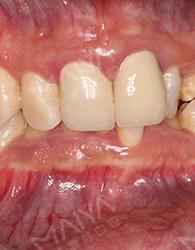

因为长相酷似央视主持人尼格买提而被称为麦芽版“尼格买提”,却在管理上遇到了瓶颈——一张口就把人吓到,常常留给别人“太凶、太高傲、不苟言笑、过于严肃、太严厉、不易亲近”的印象…

身为公司管理层,平时待人接物不仅仅代表自己,还代表着公司形象,一口鲨鱼牙怎能为麦芽代言?而且注重仪表的我,怎能允许自己在洽谈时露出钢牙套?于是我决定立即在麦芽开始隐形矫牙之旅。